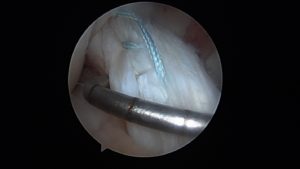

A newer way of treating ACL tears is ACL repair. This takes advantage of modern sports medicine arthroscopic techniques that allow the torn ACL to be re-anchored back in place.